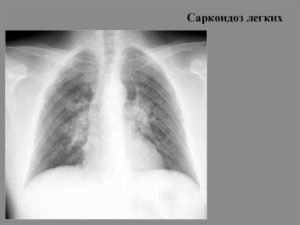

Характерные изменения при саркоидозе выявляются при рентгенографии легких, в ходе КТ или МРТ легких — определяется опухолевидное увеличение лимфоузлов, преимущественно в корне, симптом «кулис» (наложение теней лимфоузлов друг на друга); очаговая диссеминация; фиброз, эмфизема, цирроз легочной ткани. У более половины пациентов с саркаидозом определяется положительная реакция Квейма – появление багрово-красного узелка после внутрикожного введения 0,1—0,2 мл специфического саркоидного антигена (субстрата саркоидной ткани больного).

- Рентгенография и КТ — определяется симптом «матового стекла», синдром легочной диссеминации, фиброз, уплотнение легочной ткани;

- рентгеноскопия и рентгенография органов грудной клетки – позволяют обнаружить мельчайшие изменения в дыхательной системе уже на начальных этапах заболевания;

Функциональные нарушения в легких можно оценить в результате проведения рентгенографии

В случае, если у человека обнаружен саркоидоз легких, прогноз для жизни зависит от степени тяжести заболевания и обширности изменений в дыхательной системе. Функциональные нарушения в легких можно оценить в результате проведения рентгенографии.

Первая стадия – сопровождается увеличением размеров внутригрудных лимфатических узлов, изменения в анатомическом строении легкого не наблюдаются.

Вторая стадия – продолжается процесс роста лимфатических узлов, на поверхности легких можно рассмотреть темные пятна и узелки различных размеров, происходят изменения нормального строения в средних и нижних отделах легкого.

Третья стадия – легкое прорастает соединительной тканью, гранулемы начинают увеличиваться в размерах и сливаться между собой, плевра заметно утолщается.

Четвертая стадия – сопровождается глобальным разрастанием соединительной ткани, нарушениями нормального функционирования легких и других органов дыхательной системы.